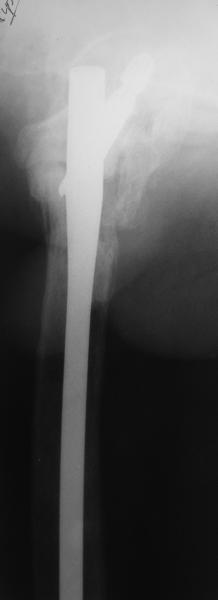

Leonid Solomin 03 Март 2009, 22:07

Возможно, пример (в приложении) поможет Вам определиться с выбором тактики лечения (у нашего пациента, кроме тугого ложного сустава вертельной области, сложная деформация н/3 бедренной кости; т.к. это не имеет значения к обсуждаемой теме - оставил "за кадром"). Как Вы видите, мы в данном случае не вводили чрескостные элементы в зону установки имплантата. При отказе от наложения опоры на таз (кстати, она не обязательно может быть громоздкая спицевая; арки со стержнями-шурупами, введенными в крыло подвздошной вполне достаточно) "не удивляйтесь", если опора со стержнями-шурупами, введенными в вертельной области в скором времени дестабилизируется, возникнет воспаление мягких тканей у чрескостных элементов. Такая опора "имеет на это право": нагрузка конечности от вершины дистального фрагмента до кончиков пальцев ляжет на нее. А двух-трех введенных рядом стержней-шурупов, как их не разноси от фронтальной плоскости, в данном

случае явно недостаточно для адекватной фиксации. + для того, чтобы выбрать оптимальные чрескостные элементы для промежуточной и дистальной опор, можете воспользоваться атласом

В приложении пример пациента, близкого по картине к тому, что представил Виктор (варус и смещение периферического отломка на поперечник кзади). Сделали как раз то, что Виктор исходно намеревался - аппаратная коррекция и затем гамма.